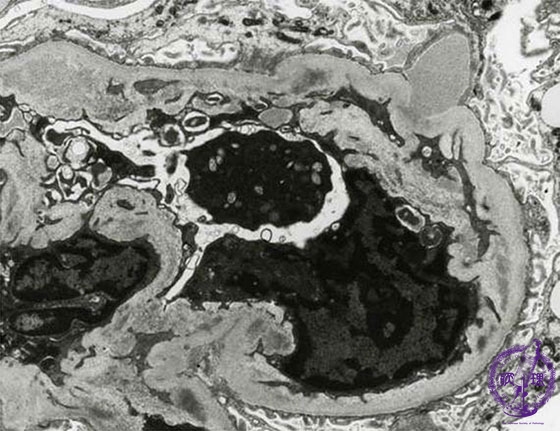

- (8)Endocapillary proliferative glomerulonephritis

Microscopic findings(electron microscopy): There are electron dense subepithelial deposits (yellow arrows). The deposits, known as humps, protrude predominantly from the subendothelial aspect.